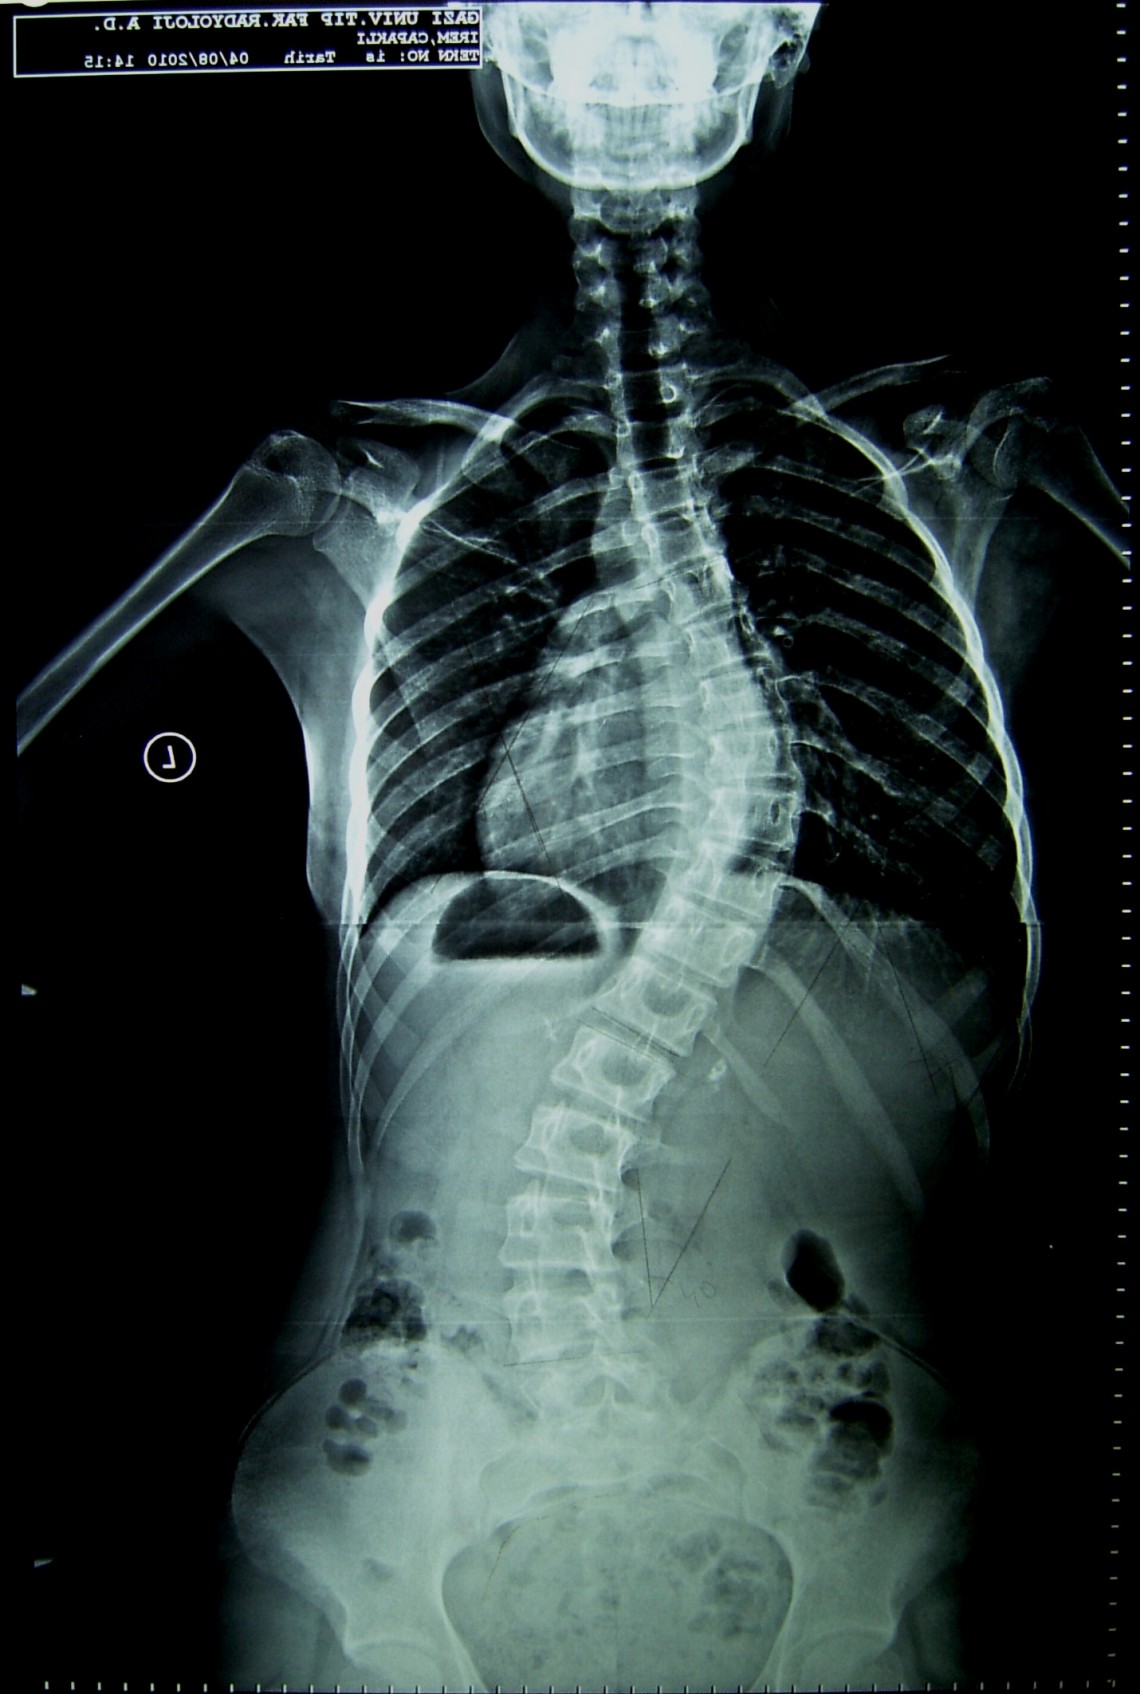

Farklı tipte skolyozu olan hastaların ameliyat öncesi ve sonrası fotoları: